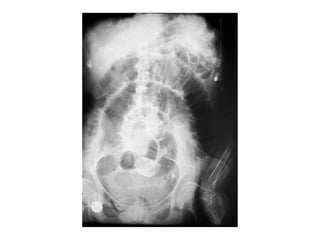

I−RADIOGRAFÍA SIMPLE

• Bipedestación y decúbito supino.

-Imágenes gaseosas por encima del obstáculo al

principio.

-Imágenes hidroaéreas tras 3-6-horas de evolución.

I-Intestino delgado distendido:

•localización central

•válvulas conniventes

II-Colon distendido:

•zonas lat y parte sup del abdomen

•haustros

–Intestino delgado

Signos Rx:

•Distención gaseosa hasta el punto de obstrucción

•Formación de niveles hidroaéreos.

•Aumento de peristaltismo en las asas preobstructivas.

•Reducción o ausencia de gas en el colon.

•Líquido en la cavidad peritoneal.

•Disposición en “escalera”de las asas dilatadas.

•Imàgenes en “collar de cuentas”.